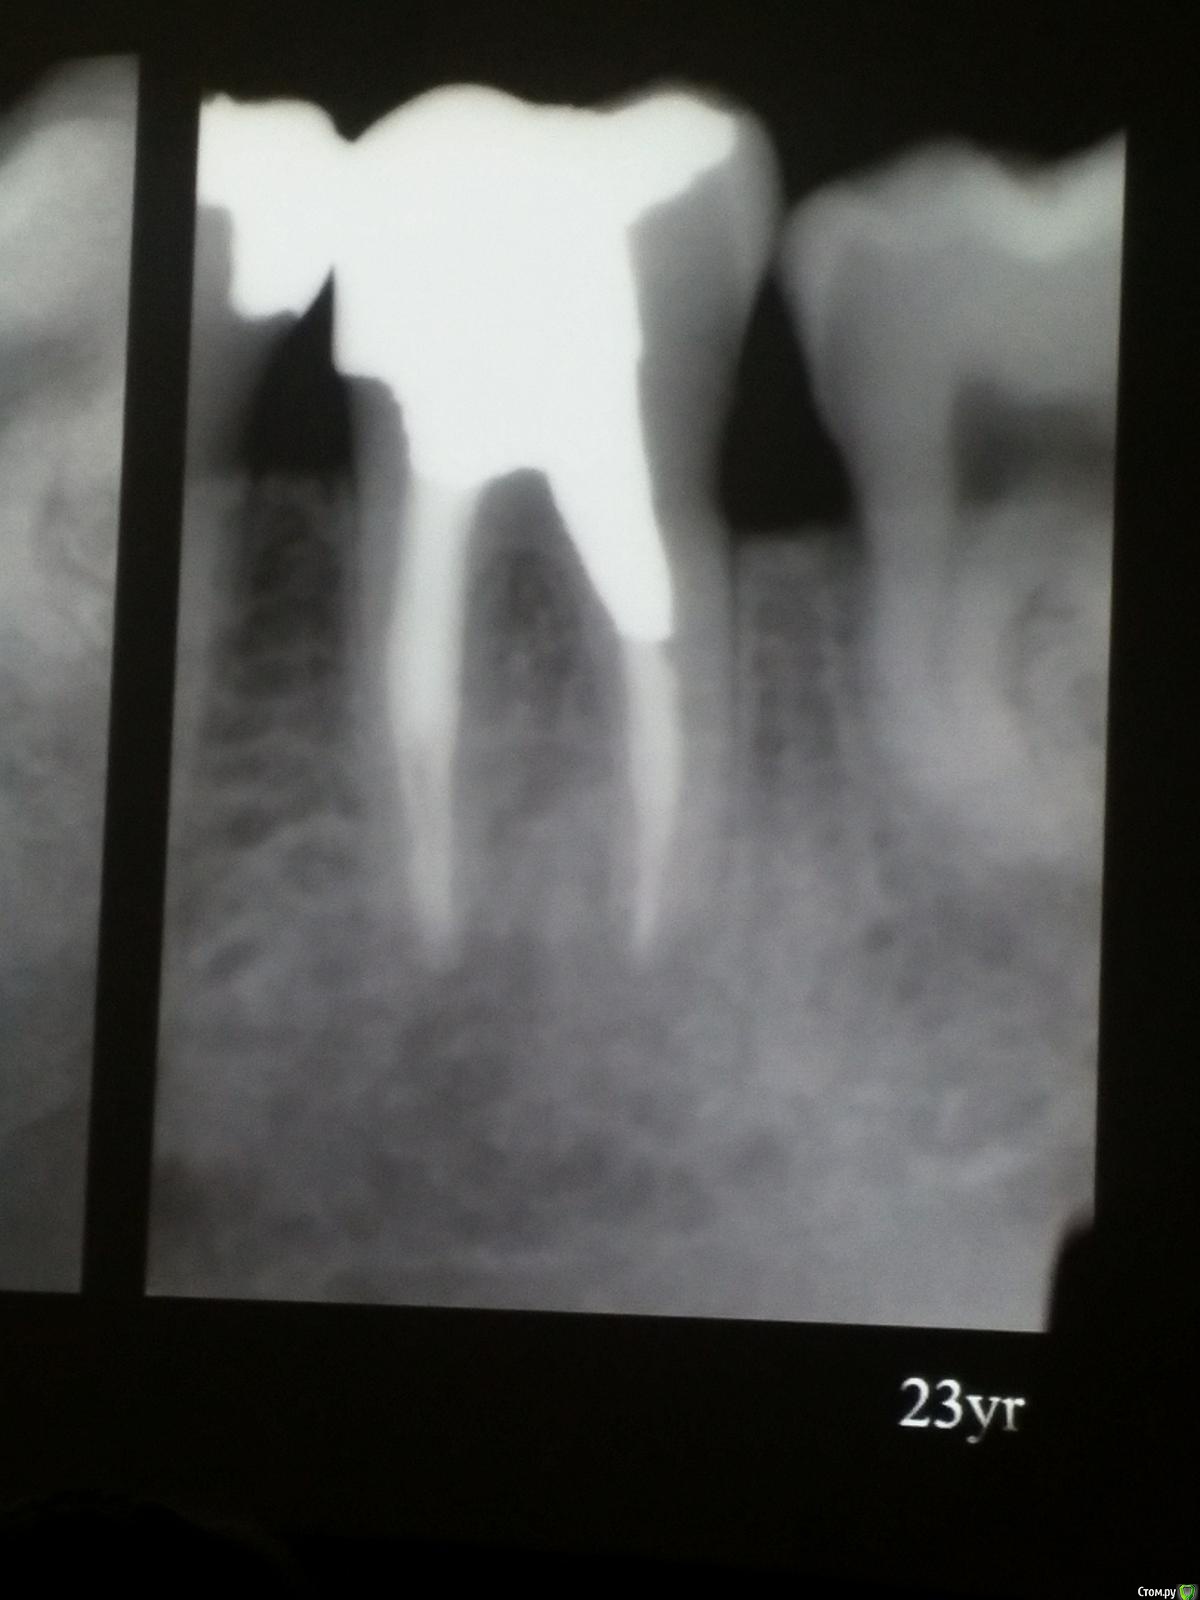

Популярный пост Kolchanov Опубликовано 11 марта, 2017 Популярный пост Поделиться Опубликовано 11 марта, 2017 (изменено) Товарищи, скажу я вам...........Вкратце. Может я где-то что-то и приврал, надеюсь, кто еще был, поправят. Честно говоря немного прибалдел от уровня Доктора. Очень, очень высоко! Приедет еще раз, пойду еще. 1) Фиссуры зондирует острым зондом и выпиливает все дотла. По факту у него уже пломбы, а не герметизация.2) Bite-wing у первичных пациентов всегда.3) Если кариес диагносцирован, то лечить его, пофиг какой он там. Эмали, дентина…4) Препарирует до твердого (или до вскрытия J ). CAD, СID… в топку. Кариес маркером не пользуется, проверяет острым зондом/экскаватором. Вычищает все дотла. Считает, что даже небольшое количество бактерий в дентине под пломбой вызывают хроническое воспаление в пульпе. С его слов у него на контроле где-то 500 вскрытий, не удивительно при таком подходе к очистке.5) Тщательная изоляция. Коффер порвался – меняет. Большое значение герметичности реставрации. под замену6) Критерии обратимости и необратимости.Гистологически, обратимый тот, что без абсцессов в пульпе, но клинически это понять нельзя, только предположить.Здесь был бы обратимый, если бы не удалил. Нет микробов в пульпе. Линия - граница обработки.Покрытие 27 лет назад. Dycal, СИЦ, композит. От дайкала одно воспоминание.7) Вскрылись. Размер перфорации, возраст и прочее не играют роли, важно только состояние пульпы, т.е. диагноз.Примеры перфораций.8) Кровотечение останавливает стерильным ватным шариком. Если останавливается, то покрытие, если нет, то пульпотомия или пульпэктомия.9) Использует гидроокись кальция (порошок), перекрывает Dycal или СИЦ. Потом восстановление Нередко под IRM, потом все убирает (через пару-тройку месяцев) и смотрит, что получилось. Порой приходится повторять! Использует и МТА, его тоже убирает.10) Наблюдение 6мес, 1 год, 2…. Все может провалиться и через месяц и через 24 года.Примеры проваловНиже - 24 года спустя появилась дуля. 11) Неравномерная облитерация полости зуба на RG (после покрытия) – признак текущего хронического воспаления, где-то остались микробы. Рекомендует эндо.12) Мостик который образуется – это не дентин! И одонтобласты не регенерируют и новые не образуются. Что это такое он и сам не знает, но раз это твердые ткани, то и наплевать.Вот фиолетовое это дентинные опилки вмурованные в розовую ткань бог знает кем сформированную.13) Пульпотомия в зубах с несформированной верхушкой и в сформированных, при подозрении на частичное поражение коронковой пульпы. Иссекается стерильным алмазным бором часть пульпы, гидроокись, временная пломба на 90 дней, после повторное раскрытие, оценка результата, восстановление в случае формирования твердых тканей. Гипохлоритом можно мыть, можно не мыть, если мыть, то 0,5-1%.14) В апикальной части пульпа чаще витальна, чем нет.15) Периапикальные поражения возникают по причине поступления токсинов микробов с током крови, а не самих бактерий.16) За апикальные расширения в полностью некротических случаях. Надо механически отодрать биопленку и срезать инфицированный дентин. На ирриганты надежды мало.17) Биопленка на поверхности в 6% случаев.Синенькие пид@расы18) Обработку проводить нежно, краун-даун. Чередовать с H-файлом, чтобы посмотреть докуда распространяется некроз.19) Патенси в витальных кейсах не колоть, сохранять витальную пульпу в констрикции!Формирование еще большего сужения в констрикции за счет сохранения витальной пульпы. Изменено 11 марта, 2017 пользователем Kolchanov 31 Ссылка на комментарий

Популярный пост Kolchanov Опубликовано 12 марта, 2017 Автор Популярный пост Поделиться Опубликовано 12 марта, 2017 Второй день.1) Дезинфекция зуба и раббер дама перед работой. Вначале установка системы, потом протирка тампоном 30% перекиси, потом протирка всего йодинолом. Потом преп, потом повторение и только потом доступ к к/к. Все старые реставрации надо убрать, кариес убрать, противник лечения через коронку.2) Гидроокись на неделю. Замешивает на стерильном физрастворе. При необходимости повторяет. Т.е. в случае сохранения свища, симптоматики, экссудации, запаха. Если свищ не исчезает после трех смен временных вложений, то хирургия.3) Пломбирует латеральной компакцией. Лучше контроль длины обтурации.4) Высушивание канала стерильными штифтами, на рабочую длину минус 1мм. После высушивания штифт оставляется на 60с. в канале и должен выйти сухим.5) Определение рабочей длины. Витальные случаи. АЛ должен три раза дать одну и ту же картинку в определенной точке + проверка RG. Девитальные случаи. На АЛ полагаться сложно, т.к. из-за наличия резорбции констрикции может врать, больше ориентируется на RG.6) Использует ЦОЭ силеры. Резорбируются при незначительном выведении. Резорбируются в канале, позволяя закрыть апекс цементоподобной тканью. Вот так вот.Случаи исчезновения силера, как за пределами канала так и в канале7) Выведение материала (не важно какого) в большом объеме способно вызвать защитную реакцию тканей. Которая должна пройти спустя некоторое время. (иногда это будет 25 лет J Случай 1ый. Студенты наломали инструментов. Периодонтит на RG через год. Резекция и гистология. Бактерий не обнаружил. Да, маленькое замечание. Каждый препарат дает 500-600 срезов. И ищет он на всех. Объем работы, конечно….Случай 2й. Его собственный. Периапикальное поражение, обнаруженное на реколле через 10 лет зажило еще через 15.8) «Функционирующий зуб» считает результатом неприемлемым. Осталась инфекция с которой надо что-то делать. То, что бактерий можно замуровать в дентинных трубочках и под пломбировочным материалом, считает неправильным. Продукты метаболизма один фиг будут просачиваться и могут поддерживать реакцию воспалительную.Случай. Синее – маленькая кучка микробов, предположительно, препятствовавших заживлению очага.9) Биопленка на поверхности корня может принимать вид кальцификатов (камней) и тут уже только хирургия в помощь. При длительном существовании свищевого хода, например.Черное - это камни вокруг апикального отверстия. И гистология их с кучей синих микробов.Здесь камни на фуркации и отсутствие заживления и свищ даже после ретроградной обработки и пломбировки.А здесь вообще чертова уйма камней. И зацените разветвление канала в этом боковом резце (последнее фото препарата). 10) Реваскуляризация.В некротических случаях дентина не образуется, т.к. одонтобластов нет и не будет новых. Образуется та самая бог знает какая ткань, которая даже и с корнем не связана может быть. Суть здоровый дентикль-петрификат. А в витальных это не реваскуляризация, а обычное формирование корня. Так что нечего тут.11) Трещины дентина.Советует расшивать, братья и сестры. Без фанатизма, если нет симптоматики, но, по возможности максимально. Если есть симптоматика, то там уже по обстоятельствам. Чертова уйма микробов там и ползет, ползет к пульпе. Надеюсь, что еще раз этот замечательный Доктор приедет. Схожу с удовольствием. 2 23 Ссылка на комментарий